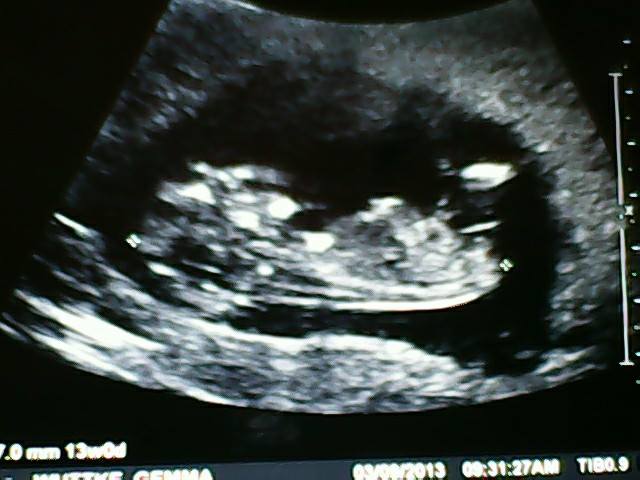

Attachment 14023Attachment 14024

There's a slight angle so I would say Boy!

Its called Ultrasound Prediction